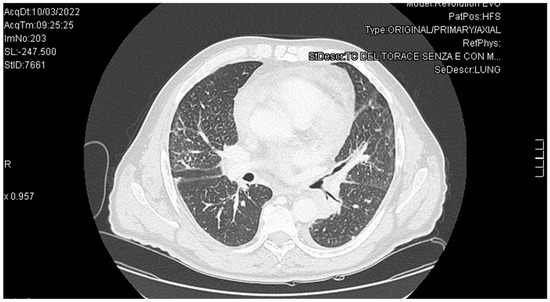

Background and Clinical Significance: Trousseau’s syndrome, characterized by recurrent thromboembolic events and non-bacterial thrombotic endocarditis, represents a severe paraneoplastic condition associated with poor prognosis in cancer patients. Due to the growing life expectancy of cancer patients, Trousseau’s syndrome is becoming more frequent. Consequently, risk of thrombosis and bleeding assessment, as well as early diagnosis and opportune therapy will gain importance. Case Presentation: We describe a case of a 63-year-old Caucasian male presenting with ischemic stroke. During management, he developed a mitral valve marantic endocarditis, and finally the diagnosis of pulmonary adenocarcinoma was performed. The case description is followed by a brief review of the relevant literature on the condition. Discussion and Conclusions: This case highlights the complexity of diagnosing and managing Trousseau’s syndrome. Early recognition, appropriate anticoagulation strategies, and the need for multidisciplinary management are crucial to improve the outcomes and the quality of life for cancer patients. Full article